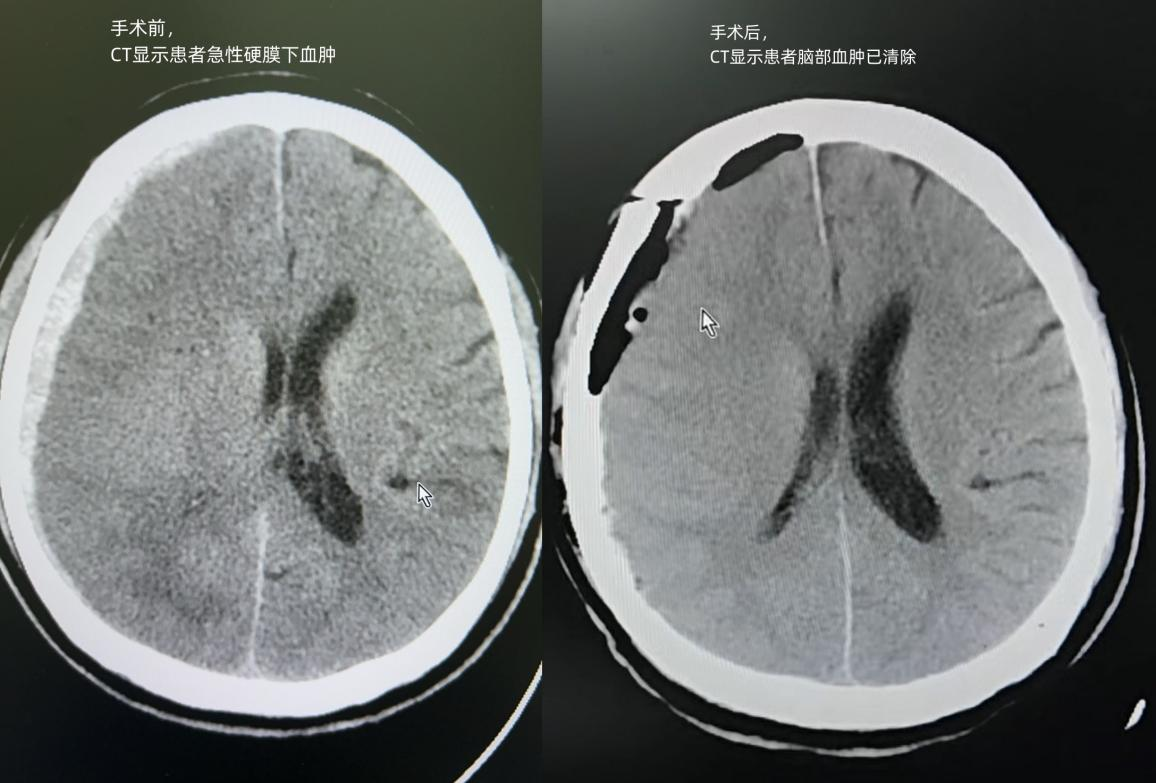

患者术前术后CT影像对比

9时08分,经过初步处置的后,急救团队将患者送到CT检查,提示右侧额颞顶枕部急性硬膜下出血,这意味着患者颅内正在出血,形成巨大血肿压迫生命中枢,必须立即手术!

下午15时35分,历时整整3个小时,这场集结了颅内血肿清除、开颅减压、脑膜修补、颅内压监测传感器置入等高难度操作的手术圆满成功。术后,患者瞳孔恢复正常,生命体征平稳并转入病房。这场在国庆假期中完成的紧急手术,不仅清除了一颗危及生命的“颅内炸弹”,更守护了一个家庭的希望。